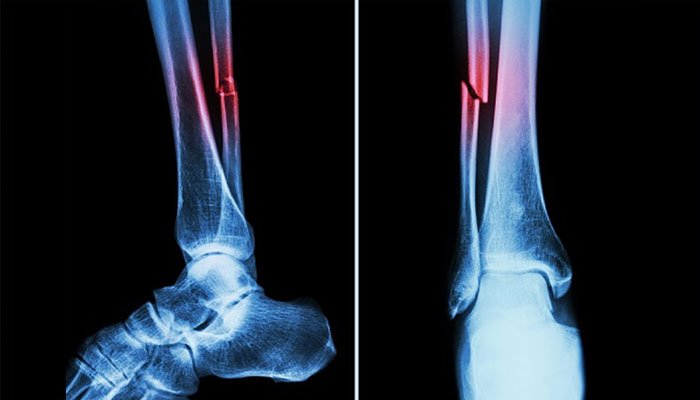

بیجنگ : چین کے محققین نے ہڈیوں کے فریکچر کو منٹوں میں جوڑنے والا انقلابی سپر گلو تیار کر لیا ہے، جو روایتی طور پر کئی ماہ کے بعد جوڑنے والی ہڈیوں کے علاج کو چند منٹوں میں ممکن بنا دیتا ہے۔

چین کی ژے جیانگ یونیورسٹی کے ماہرین نے اس سپر گلو کو بون-2 کا نام دیا ہے، جو پہلے ہی 150 سے زائد کامیاب طبی تجربات میں استعمال ہو چکا ہے، ماہرین کے مطابق یہ چپکنے والا مادہ محض ایک انجکشن کی صورت میں ٹوٹے ہوئے ہڈی کے ٹکڑوں کو صرف تین منٹ میں جوڑ دیتا ہے۔

ہانگزو کے آرتھوپیڈک سرجن ڈاکٹر لن شیان فینگ کے مطابق عام حالات میں ہڈی کے فریکچر کو جوڑنے میں مہینوں لگتے ہیں اور اس دوران مریض کو دھات کی پلیٹس، آپریشن اور پیچ لگانے جیسے تکلیف دہ مراحل سے گزرنا پڑتا ہے، لیکن بون-2 نے اس عمل کو آسان اور تیز رفتار بنا دیا ہے۔